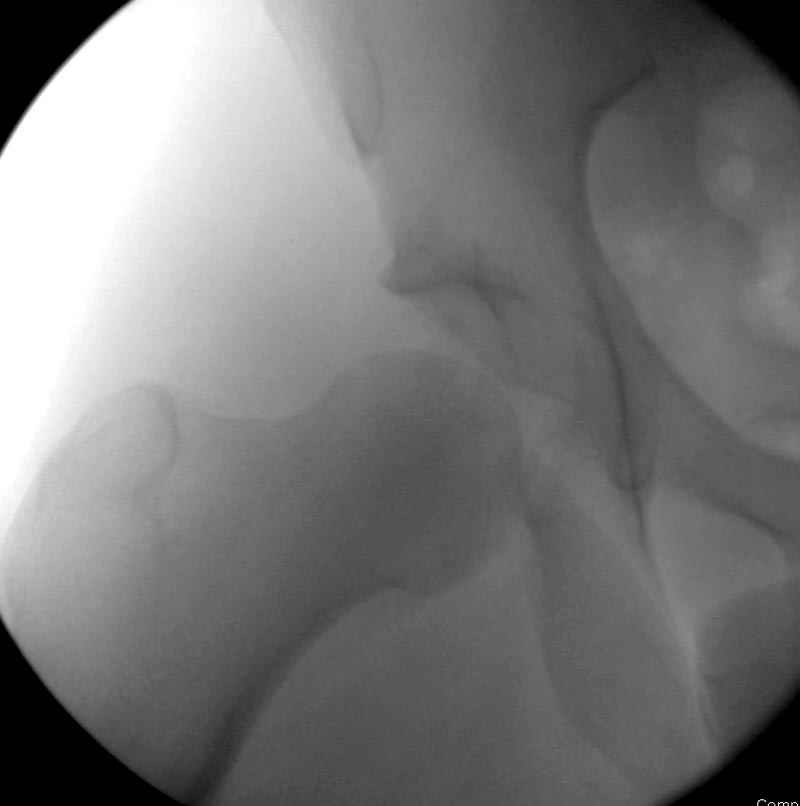

7:30 начало операции, больной на спине, попытка репозиции после анестезии N3, укладка больного на боку, доступ Kocher- Langenbeck, состояние седалищнего нерва около 2.5см кровоподтек, через joistick головка бедра приподнята, освобовождение сустава, фрагмент заднего края более 3х4 см репонирован на свое место. После промывания

сустава, репозиция вывиха (N4), фиксация фрагмента 2.7(4) мм шурупами и допольнительно реконструктивной пластиной на 8 дырок, фиксация 3.5мм шурупами проксимально и дистально.

Интраоперционные N5 косая запирательная и N6 подвздошный снимок